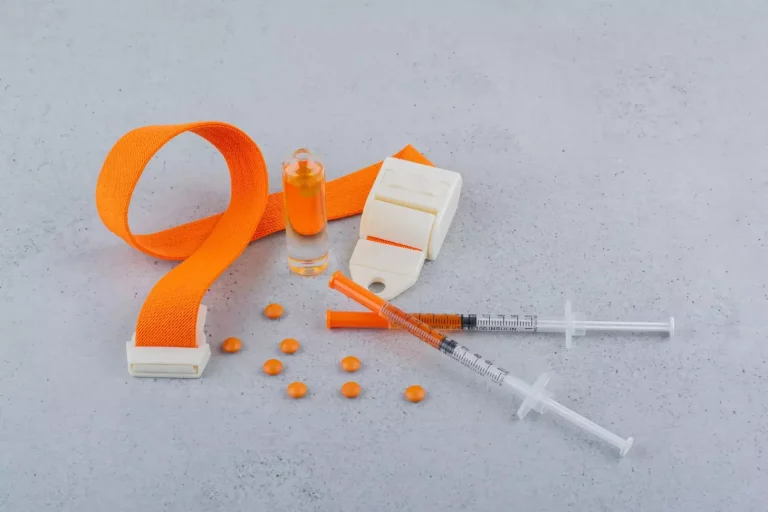

Prescription Medications and Their Effects

Medicines are key in treating back and leg pain. Muscle relaxants and pain relievers help ease symptoms. Gabapentin, for example, can help with sciatica nerve pain. Always follow your doctor’s advice to avoid side effects.

Steroid Injections and Nerve Blocks

Steroid injections and nerve blocks are good for reducing pain and swelling. Steroid injections go directly into the painful area to lessen swelling and pain. Nerve blocks inject medication into nerves to stop pain signals to the brain.